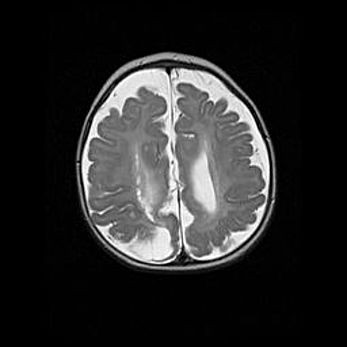

Сообщающаяся гидроцефалия. Кистозная энцефаломаляция головного мозга.

Возраст: 3 месяца 4 дня

Вес: 3100 г

Пол: женский

Окружность головы: 34 см

Срок гестации: 31 неделя

Кистозная энцефаломаляция головного мозга - одна из форм поражения головного мозга в детском возрасте. Характеризуется возникновением множественных и распространённых кист в коре, белом веществе и подкорковых образованиях головного мозга у плодов, новорождённых и детей раннего возраста. Развитие кистозной энцефаломаляции связано с внутриутробной асфиксией и гипотонией, родовой травмой, тромбозом синусов, пороками развития сосудов, инфекциями, сепсисом и другими причинами. Наиболее значимые инфекционные агенты: вирусы простого герпеса, цитомегалии, краснухи, токсоплазмы, энтеробактерии, золотистый стафилококк и другие.